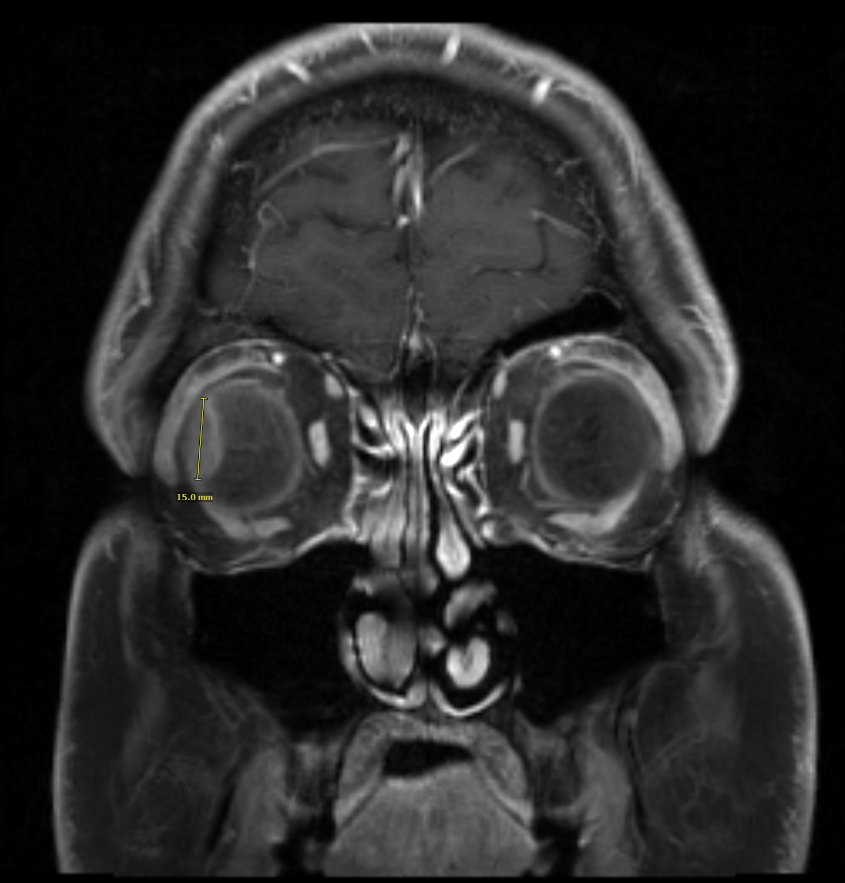

Day two began before the sun with a 5 a.m. wake-up call. Back at Mayo, I had another MRI to face—this time, of my eyes. And yes, that also meant another IV. (Needle count: four, so far.) This MRI gave the team a close-up of Lenny’s hideout, capturing every detail. This time, I managed to stay awake, helped by the “head cage” they placed over me—a contraption reminiscent of Nicholas Cage in The Wicker Man, only with fewer bees.